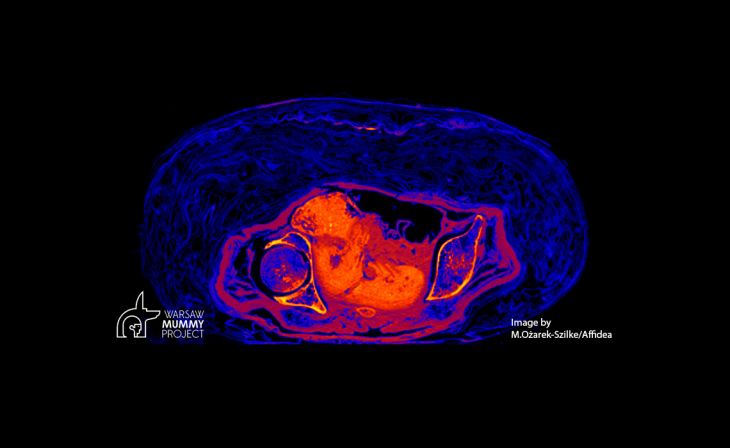

El feto de 28 semanas descubierto intacto en el cuerpo de una momia egipcia en abril de 2021, se conservó hasta nuestros días por la acidificación del cuerpo de la madre mientras se descomponía.

Durante el proceso de momificación, se cubrió a la difunta con natrón, un sodio natural en Egipto, para secar el cuerpo. La colocación y llenado del cuerpo con natrón limitó significativamente el acceso de aire y oxígeno. El resultado final es un útero casi herméticamente sellado que contiene el feto. El embrión se encontraba en un ambiente comparable al que conserva cuerpos antiguos hasta nuestros días en los pantanos.

El cambio de un ambiente alcalino a ácido condujo a la descomposición parcial de los huesos fetales, especialmente al lavado de minerales, de los cuales no había mucho de todos modos, porque la mineralización es muy débil durante los dos primeros trimestres del embarazo y se acelera más tarde, según el nuevo estudio, publicado en Journal of Archaelogical Science.

Entonces, dijo, sucedió otro proceso de momificación, la mineralización del feto. Durante el secado, los minerales de los huesos, que se disolvieron en el líquido amniótico, se depositaron en los tejidos blandos del feto y el útero. Como efecto, están el feto y el útero altamente mineralizados. Es por eso que tienen un alto valor unitario de Hounsfield (la escala de Hounsfield es una escala cuantitativa para describir la radiodensidad) registrada en los datos de TC.